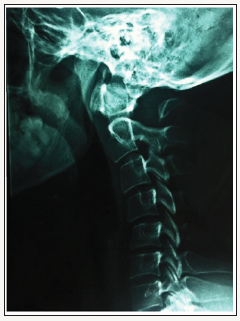

Simple radiography (Rx) revealed the existence of a partial defect in the posterior arch of C1 with a preserved posterior tubercle (Currarino type D) (Figure 1). We verified the stability of the tubercle through radiography in flexion and extension (Figure 2). Computed tomography (CT) images with three-dimensional (3D) reconstruction demonstrated the absence of the posterior arch and the presence of a persistent posterior tubercle (Figure 3). No evidence of compression of the spinal cord was shown on magnetic resonance imaging (Figure 4). The patient benefited from a symptomatic treatment with anti-inflammatory and analgesic drugs. Her symptoms decreased within 48 hours. She was asked to avoid contact sports, athletic activities and any activity or situation which could cause the cervical hyperextension.

Figure 1:Lateral radiograph of the cervical spine showed a defect in the posterior arch of the atlas, with persistent posterior tubercle.